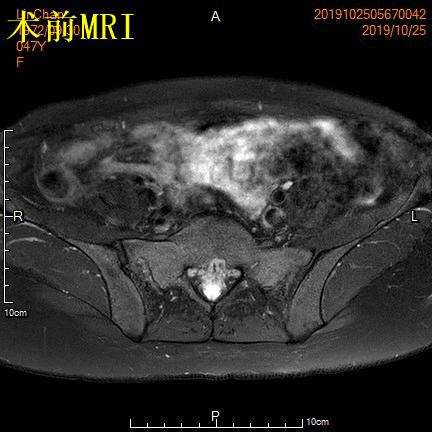

中年患者,发现“子宫腺肌症”10年余,近5年痛经、月经量增多等症状明显加重,导致贫血,严重影响生活质量。

- 术前彩超、磁共振检查显示子宫明显增大,子宫前壁可见弥漫型子宫腺肌症病灶,合并粘膜下、肌壁间子宫肌瘤。

横断位

- 术后患者痛经、月经量过多症状迅速缓解,生活质量明显改善。